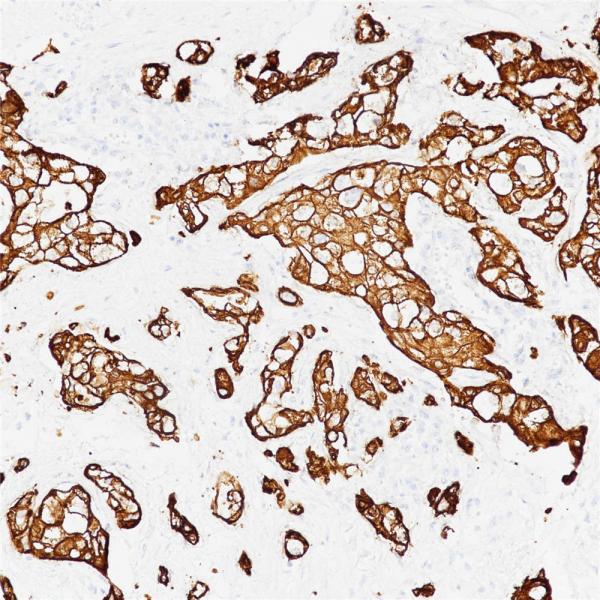

Cytokeratin 7

BP6060